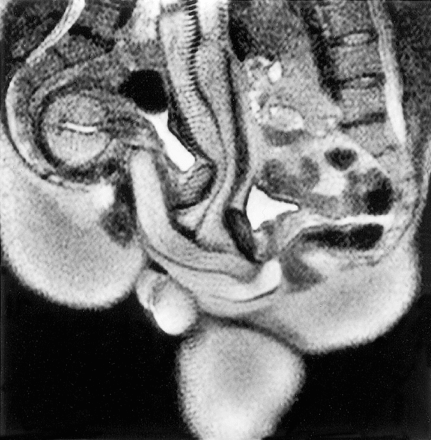

これがMRI撮影したセックス中の姿です

よく勃ったな…

>これがMRI撮影したセックス中の姿です

>よく勃ったな…

写り的にも確かにMRIだな

刺さった状態を撮影する間維持したのか…

これに加えて最近は潮吹きの液体成分すら研究されてるからこういうのあってもまあおかしくない気はする

ちなみに液体の9割は尿由来の成分らしくて多くの例でオーガズムの後に女性側の膀胱も空っぽになってたらしい